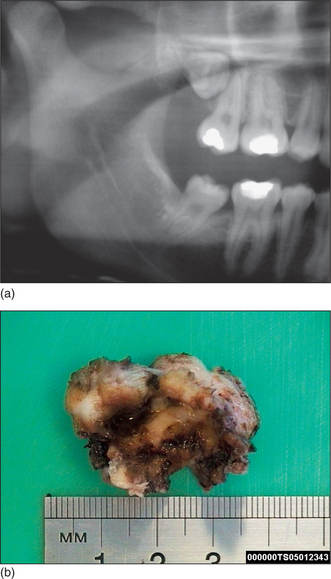

image

Fig. 5.7 Mesioangular impacted lower left third molar with distal caries on adjacent molar. Note horizontal impacted right third molar.

Page 51

Fig. 5.8 Severe periodontal bone loss between an impacted third molar and carious second molar.

Fig. 5.9 Dentigerous cyst surrounding impacted third molar.